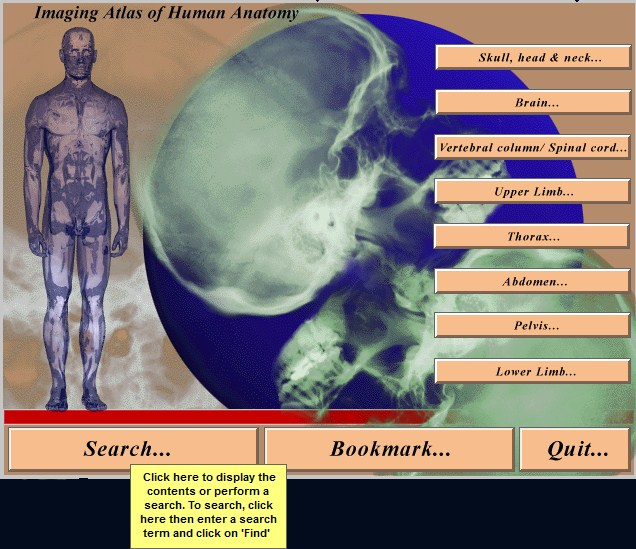

Windows Совместимость с Vista: неизвестно Системные требования: IBM or compatible PC, 486SX, 8MB RAM, 640 × 480 display, 256 colors, double speed CD-ROM drive, Microsoft Windows 3.1 or later, optimum: Pentium processor, 800 × 600 display, more than 256 colors, ISBN 0-7234-2187-0, St Louis, Mo, Mosby, 1995 Язык интерфейса: только английский Таблэтка: Не требуется Описание: This CD-ROM provides a detailed atlas of radiologic anatomy in all forms, including plain films, magnetic resonance (MR) imaging, computed tomography (CT), venography, and angiography. It is formatted to present a concise atlas, cephalad (skull) to caudad (feet). The disc is easy to work with, and I did not have any trouble setting it up. The graphics and table of contents are laid out well. Navigating the various parts is relatively simple. The opening graphics are well displayed, allowing instant access to pictures or the table of contents; therein lies the simplicity of finding an anatomical part of the body to review. Each screen contains a picture of the radiograph accessed, key landmarks (with a glossary that can be turned off), related slides that can easily be accessed, and a self-exam. Диск содержит более чем 3500 радиографических изображений нормальной анатомии, включая обычные рентгенограммы, КТ, МРТ, ангиограммы, артериограммы и видео УЗИ. Исчерпывающий уровень анатомических ориентиров с возможностью самоконтроля. Издание рассчитано прежде всего на рентгенологов. Доп. информация: Поскольку издание старое, придется установить древнюю версию Quick Time - 2.0.3.51 (есть на самом диске). Набор в группу «Хранители» - Помогите сохранить редкие раздачи Программы и Дизайн » Системы для бизнеса, офиса, научной и проектной работы » Медицина - интерактивный софт